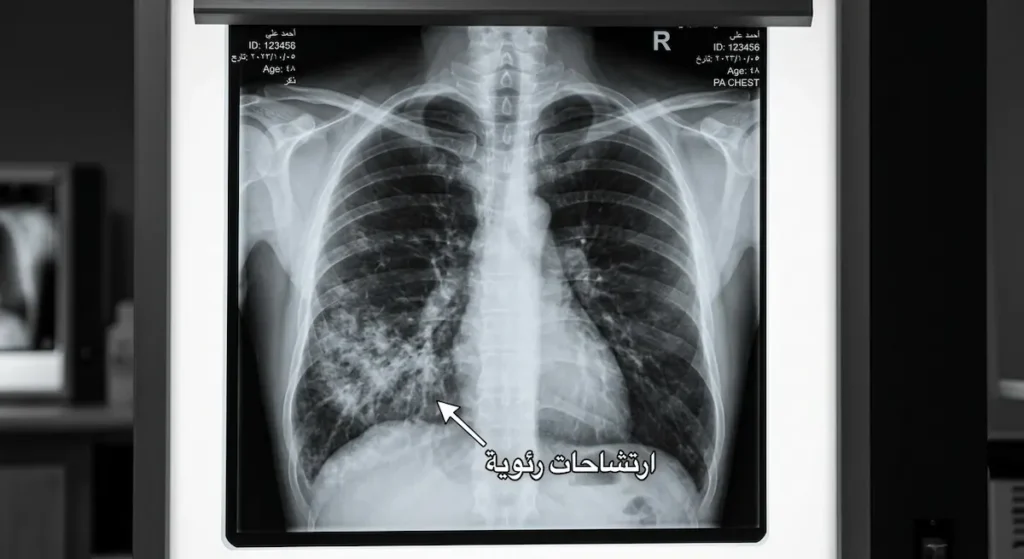

بعد مرور ساعات — وأحياناً يوم كامل — تبدأ المرحلة الالتهابية الثانية. هنا تتفاقم الوذمة الرئوية وتظهر ارتشاحات واسعة في صور الأشعة. حرارة الجسم قد ترتفع، وقد ينخفض ضغط الدم نتيجة التسرب الوعائي الشديد. في أسوأ السيناريوهات، يتطور الوضع إلى متلازمة الضائقة التنفسية الحادة (ARDS) مع فشل تنفسي يستدعي تهوية ميكانيكية مطولة.

صور الأشعة السينية للصدر (Chest X-ray) تُظهر ارتشاحات رئوية (Pulmonary Infiltrates) غالباً في الفصوص السفلية والخلفية للرئتين، وهي المناطق التي يتجمع فيها السائل المشفوط بفعل الجاذبية عندما يكون المريض مستلقياً على ظهره. في البداية قد تبدو الأشعة طبيعية، ثم تتطور الارتشاحات خلال ساعات. هذا التأخر في الظهور الشعاعي هو فخ تشخيصي معروف يجب أن يكون كل طبيب طوارئ على دراية به.

من حيث المظهر الشعاعي: متلازمة مندلسون تُظهر ارتشاحات منتشرة ثنائية الجانب تشبه الوذمة الرئوية. الالتهاب البكتيري يُظهر عادة بؤرة تكثيف (Consolidation) في الفص السفلي الأيمن غالباً.